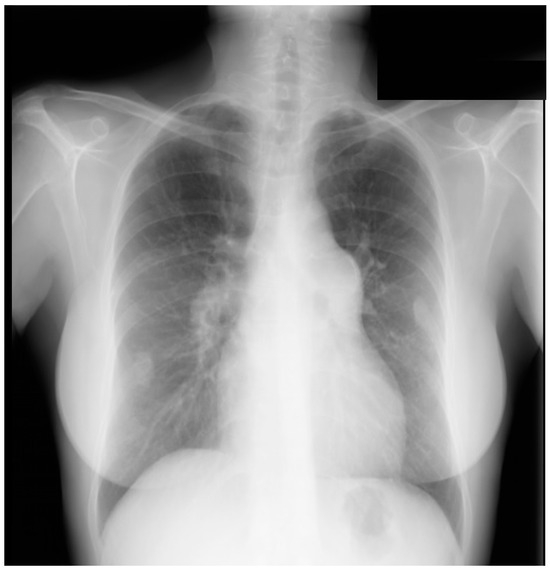

Figure 3.

Lateral chest X-ray of a pericardial cyst: This is the lateral chest X-ray of the same-40 year-old female with a right cardiophrenic angle pericardial cyst. This image demonstrates that this pericardial cyst (blue dots) is located anteriorly in the chest and adjacent to the heart, and explains the silhouette sign on the posteroanterior chest X-ray. In this image, because the cyst and the heart are superimposed, their radiodensities are summed and the cyst appears denser than the rest of the heart that it does not overlie.